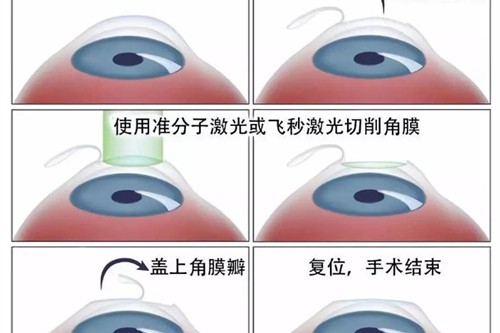

在可靠技术方面,雷医生擅长玻璃体视网膜手术,对复杂性视网膜脱离、糖尿病视网膜病变、黄斑裂孔、黄斑前膜等疾病有独到的治疗经验。

她采用小创口玻璃体切割技术,结合较可靠的眼科检查设备,为患者制定个性化治疗方案。

小创口玻璃体切割术:使用25G/27G超小创口系统,创伤小、修复快